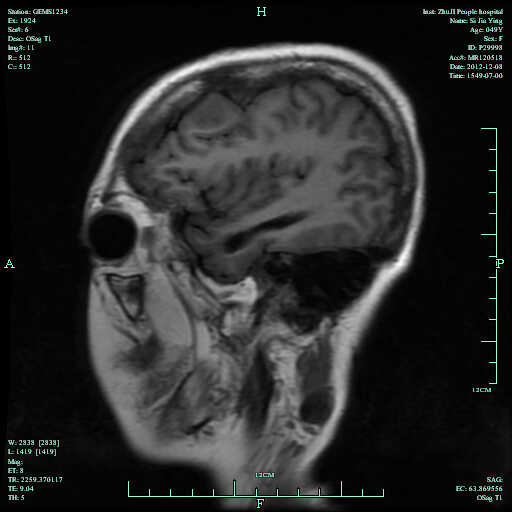

一、神经系统病变:因为脊柱强直及骨质疏松,相当容易诱发颈椎脱位和察觉脊柱骨折,而带来脊髓压迫症;如发生椎间盘炎则导致剧烈疼痛;强直性脊柱炎后期能够侵犯马尾,发生马尾综合征,而构成下肢或者是臀部神经根性疼痛;骶神经分布区感染丧失,跟腱反射减弱及膀胱和直肠等运动功能障碍。推荐文章:强直性脊柱炎有哪些症状

2、强直性脊柱炎患者普遍都伴有骨质疏松,以椎体改变比较明显,并且多伴有骨质增生、韧带骨化和骨关节硬化等,一般常常是骨质增生和骨质疏松同时并存,以脊柱各椎体表现为明显。强直性脊柱炎晚期有少数患者马尾神经受损出现慢性进行性马尾神经综合征。